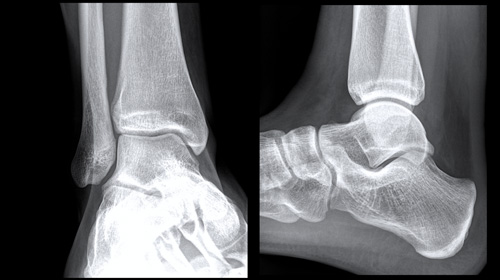

Foot and Ankle cases